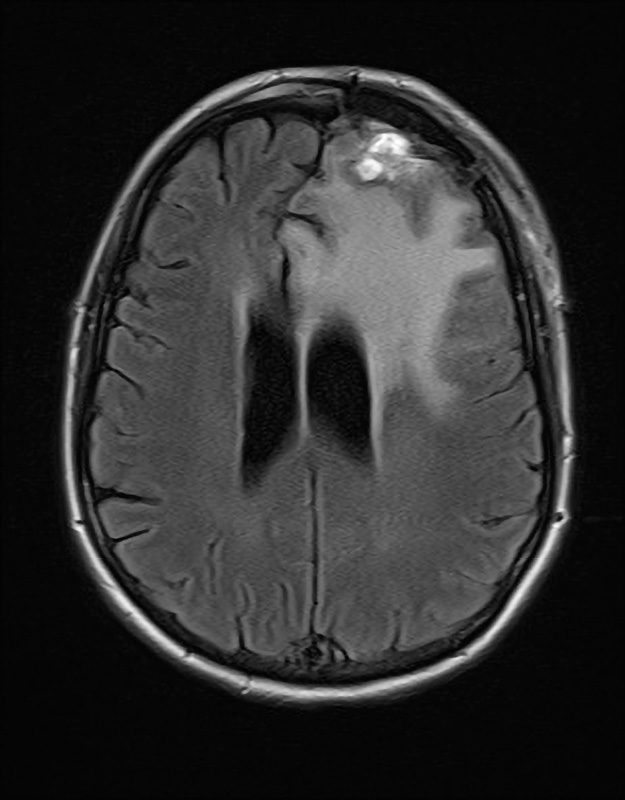

Figuur 2. Patiënte A, 10 dagen na resectie meningeoom links frontaal (2 dagen na heropname)

Afname van de massawerking op het ventrikelsysteem en afname van de midlineshift; lichte diffusierestrictie in de resectieholte (niet ongebruikelijk); geen aanwijzingen voor complicaties